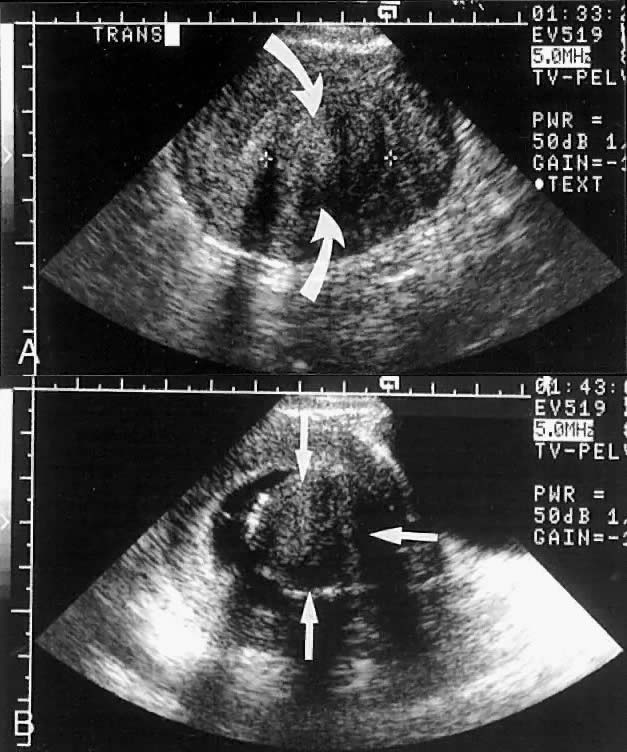

It appears that sonohysterograms are not more sensitive for the detection of submucous leiomyomas than transvaginal scans without infusion. However, this is deceptive, because the degree of myometrial involvement frequently cannot be accurately mapped without saline infusion. This problem can lead to inappropriate case selection (Figs. 8 and 9).

Fig. 8. A. A centrally located leiomyoma is identified (straight arrows). The endometrial stripe is poorly seen. B. After saline infusion (curved arrows), a 3-cm submucous leiomyoma with minimal myometrial extension (category T-I) is identified.

Fig. 9. A. A centrally located leiomyoma is identified, but the endometrial stripe is poorly seen. B. After saline infusion, a submucous leiomyoma with more than 50% penetration into the myometrium (category T-II) is seen.